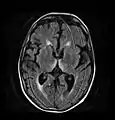

Axial MRI B=1000 DWI image showing hyperintense signal indicative of restricted diffusion in the mesial dorsal thalami.